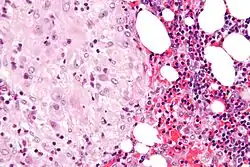

The decidua has a histologically-distinct appearance, displaying large polygonal decidual cells in the stroma. These are enlarged endometrial stromal cells, which resemble epithelium (and are referred to as "epithelioid").

Its leukocyte population is distinct, with the presence of large endometrial granular leukocytes being predominant, while polynuclear leukocytes and B cells are scant.

The large granular lymphocytes (CD56 bright) are called uterine natural killer cells| (uNK cells).

Acute choriodeciduitis, with neutrophils seen in the chorion and decidua.